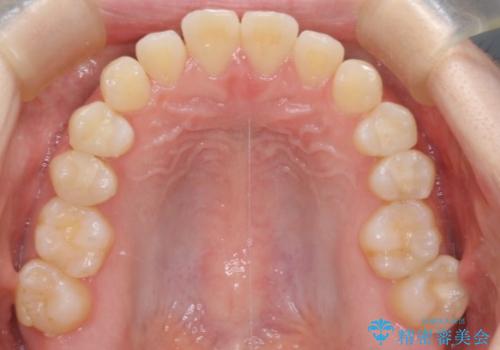

前歯と奥歯のガタガタを矯正で改善

- 患者様は、前歯と奥歯のガタガタ(叢生)を改善し、正面から見た時の歯並びを美しく整えたいとのご要望で来院されました。診断の結果、非抜歯での矯正が可能と判断し、インビザラインを使用する治療計画を立案しました。透明な矯正装置で目立ちにくい治療を行いながら、前歯と奥歯の両方を整列させることを目標にしました。

インビザラインを用いて、前歯の見た目を重視しつつ、奥歯のガタガタも改善しました。特に正面から見た際の美しい歯列を意識し、段階的に歯を移動させることで、全体の調和を図りました。治療中は、適切な装着時間を守ることや、装置の清潔を保つことが重要でした。また、歯肉や歯列全体に無理な負担がかからないように移動を管理しながら治療を進めました。結果として、前歯と奥歯がきれいに並び、見た目にも機能的にも満足いただける仕上がりとなりました。